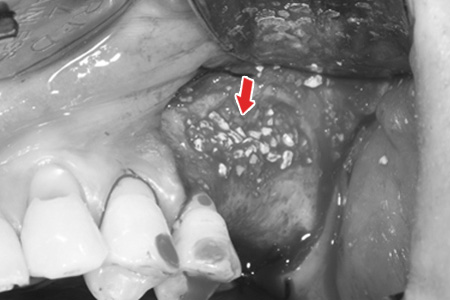

ǵ Ż ݴϿ öƮ ĸؾ ϴµ 쿡 ϴ üԴϴ. ݴ ο ο ǵ̶ ִµ ݴ öƮ ü 쿡 ̽ ؼ ǵ ణ ø ʿ䰡 ֽϴ. ü ǵ Ż̶ մϴ.

ǵ Ż ̿Ͽ ΰ̽ Ͽ öƮ ĸ ִ ̸ Ȯ ָ öƮ ĸϿ ǵ ǵ帮 ʰԵǰ öƮ ˸ þ Ǿ öƮ ĸ ϴ.

ǵ Ż 3CT ij Կ Ͽ ǵ ¿ ũ, λ β ľϿ ʿ ȯڿԸ üմϴ.